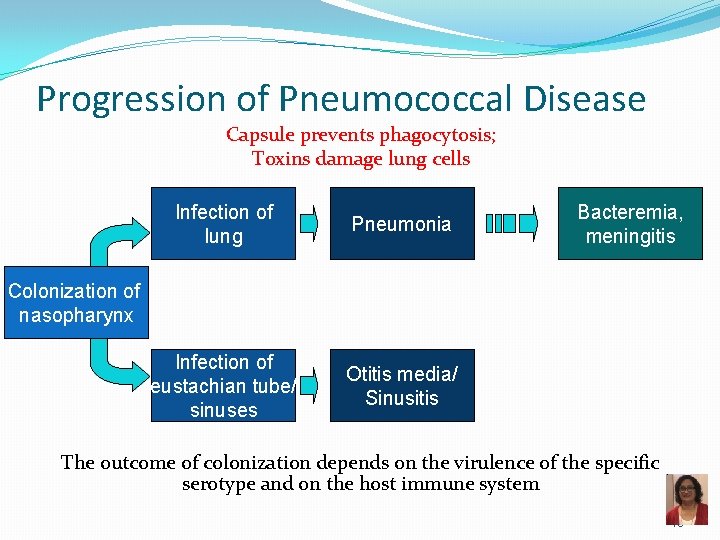

Progression of Pneumococcal Disease Capsule prevents phagocytosis; Toxins damage lung cells Infection of lung Pneumonia Infection of eustachian tube/ sinuses Otitis media/ Sinusitis Bacteremia, meningitis Colonization of nasopharynx The outcome of colonization depends on the virulence of the specific serotype and on the host immune system 18